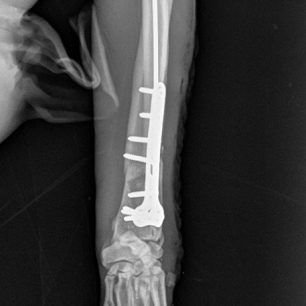

LeilaGnomatefsiKtiniatroΗ γνωμάτευση του κτηνίατρου που έκανε το ορθοπεδικό χειρουργείο.

Η κα Μακρή δημοσίευσε σήμερα στο facebook την γνωμάτευση του κτηνιάτρου σχετικά με την εξέλιξη της υγείας του ζώου. Σε αυτή αναφέρεται ότι: «Ο σκύλος έφερε συντριπτικά ενδοαρθρικά κατάγματα με μετατόπιση στο κάτω τρίτο του αριστερού αντιβραχίου και στο κάτω τρίτο του αριστερού μηριαίου. Ολοκληρώθηκε με επιτυχία η πρώτη χειρουργική επέμβαση που αφορούσε την ανάταξη και οστεοσύνθεση του αριστερού αντιβραχίου. Λόγω της σοβαρότητας του κατάγματος η διάρκεια της χειρουργικής επέμβασης ήταν 4 ώρες και 25 λεπτά και ο σκύλος ανένηψε φυσιολογικά».